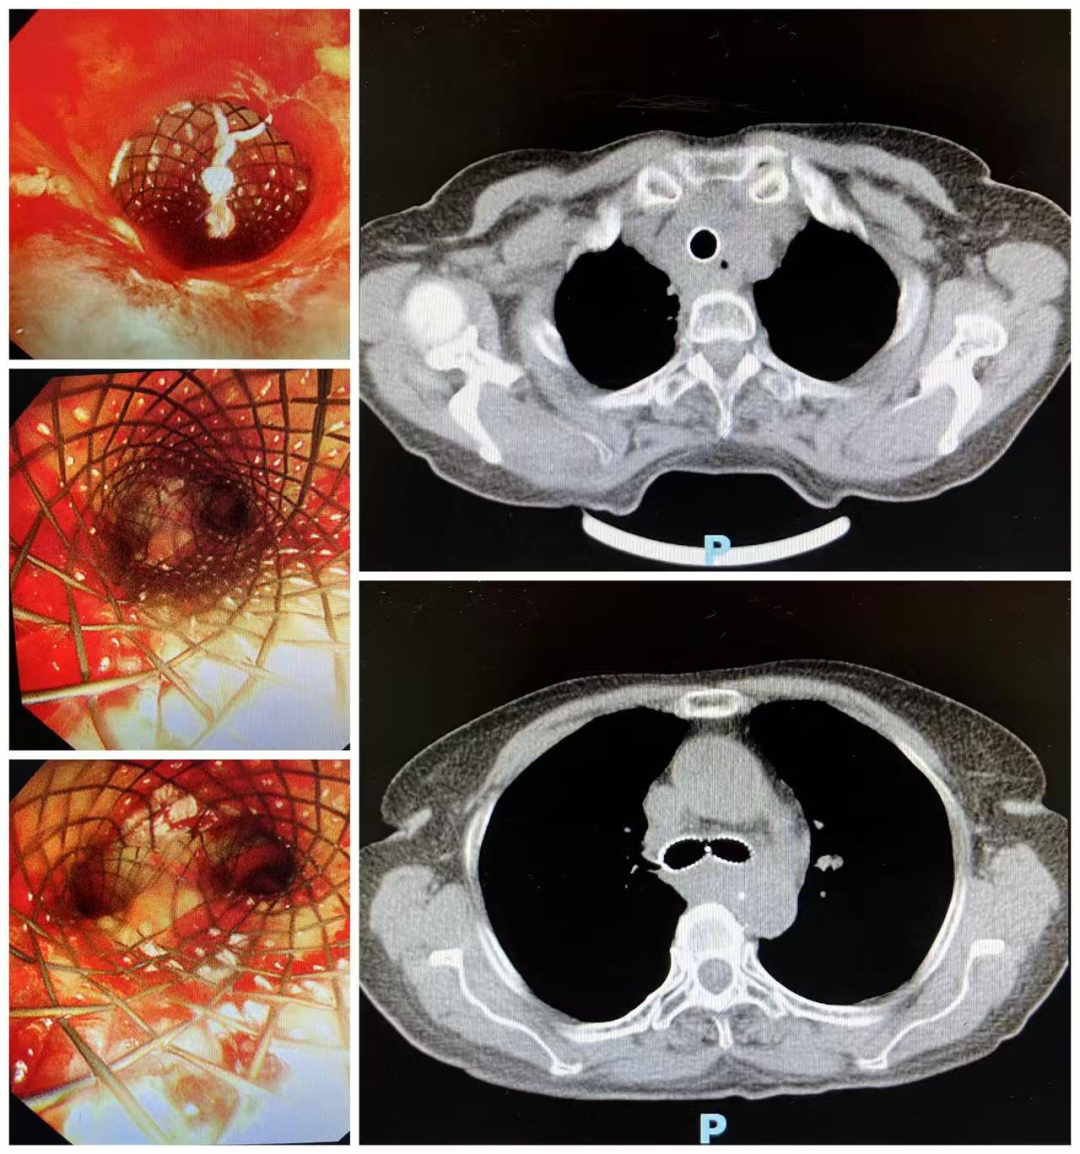

9月12日,在多学科密切配合下,患者在全麻状态下成功接受了硬质气管镜下Y型金属覆膜支架置入术,撑开了被肿瘤挤压的“生命要道”。术后,患者呼吸困难症状显著改善,当日转入重症监护室观察,次日病情稳定转回普通病房。复查影像及气管镜显示,气管管腔通畅,支架位置理想、扩张良好,未见明显并发症。患者术后恢复顺利,5天后康复出院。

患者术后胸部CT及镜下图片

该手术不仅有效解除了患者气道狭窄所致的呼吸困难,也避免了食物经瘘口进入气管引发的反复肺部感染,显著提升了患者的生活质量。